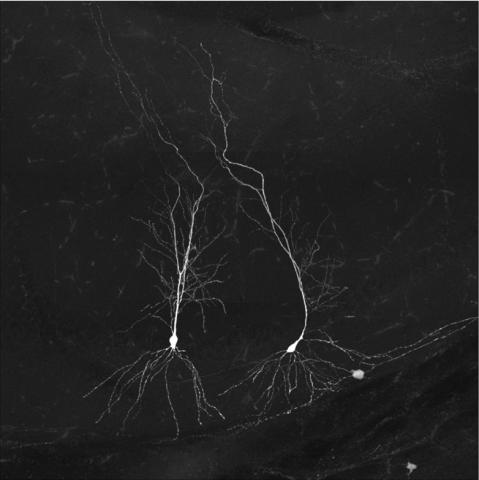

A neurofibrillary tangle

Neurofibrillary tangle in post-mortem Alzheimer’s brain. Credit: Spires-Jones Lab, UK DRI at Edinburgh